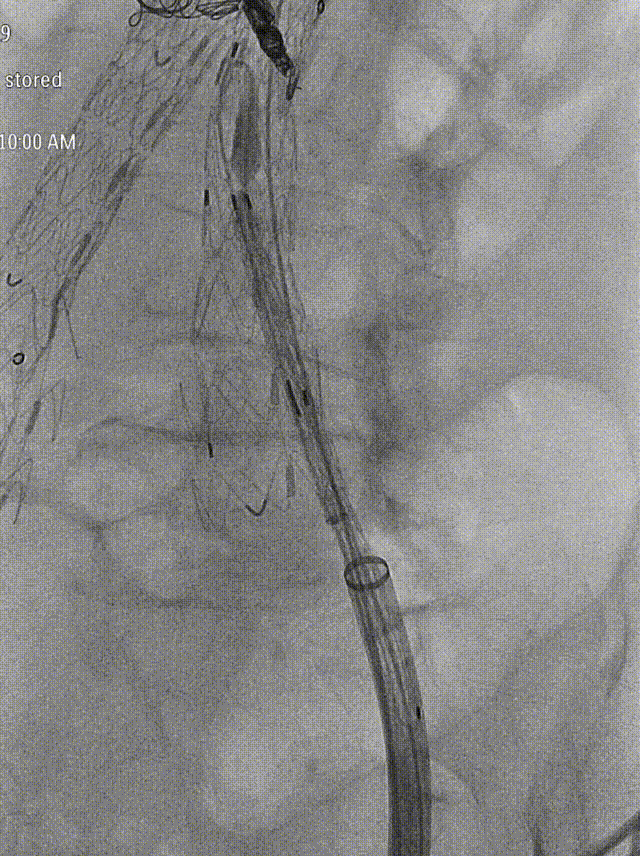

将20Fr鞘沿泥鳅导丝硬头端送至IBE主体支架分叉处,再导入GORE DSF1245鞘经20Fr鞘沿泥鳅导丝翻山至短腿开口。

gore医疗怎么样「漫腹精论」独具匠心 推陈出新——同侧IBE支架内翻山重建髂内动脉治疗EVAR术后内漏病例报道_https://www.jmylbn.com_新闻资讯_第16张

翻山至IBE短腿开口

gore医疗怎么样「漫腹精论」独具匠心 推陈出新——同侧IBE支架内翻山重建髂内动脉治疗EVAR术后内漏病例报道_https://www.jmylbn.com_新闻资讯_第15张

释放IBE主体到长腿

导丝配合导管沿DSF1245鞘选至髂内远端,交换Amplatz导丝,植入GORE髂内分支支架HGB161207(16mm-12mm-70mm),退鞘,手推造影确认位置后释放。髂外动脉起始段及髂内动脉中段见受压。导入球囊(8mm*40mm)扩张髂内动脉狭窄处,并予以CODA球囊扩张髂外动脉起始段狭窄处。

gore医疗怎么样「漫腹精论」独具匠心 推陈出新——同侧IBE支架内翻山重建髂内动脉治疗EVAR术后内漏病例报道_https://www.jmylbn.com_新闻资讯_第18张

植入髂内分支